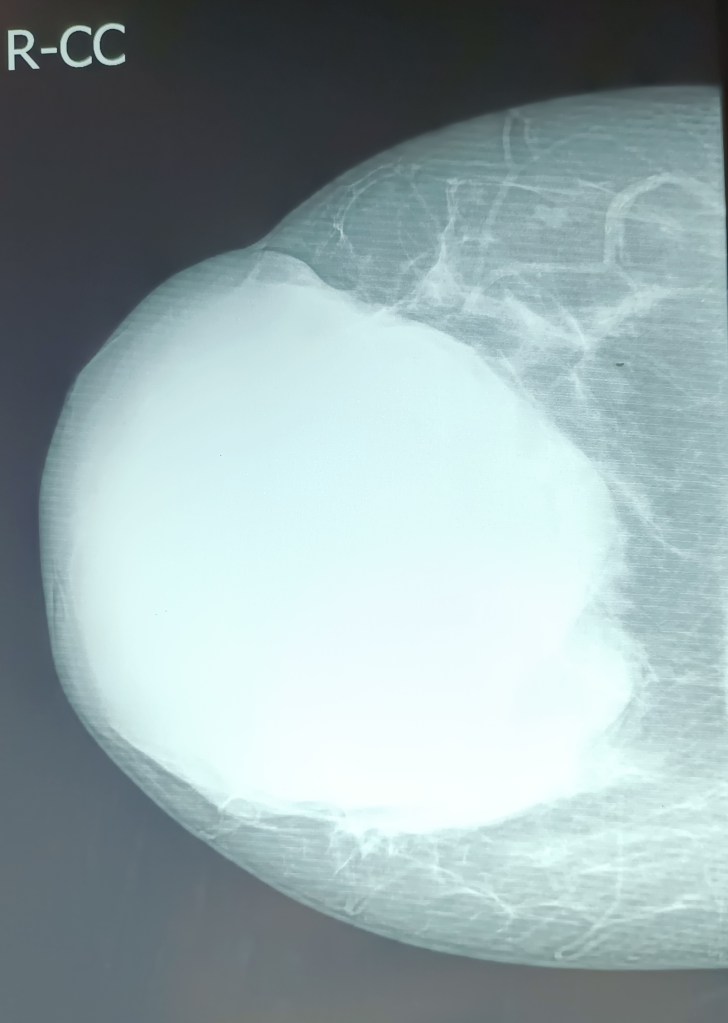

A big phyllodes tumor of the right breast removed at a simple total mastectomy (Dr Jagga’s case).